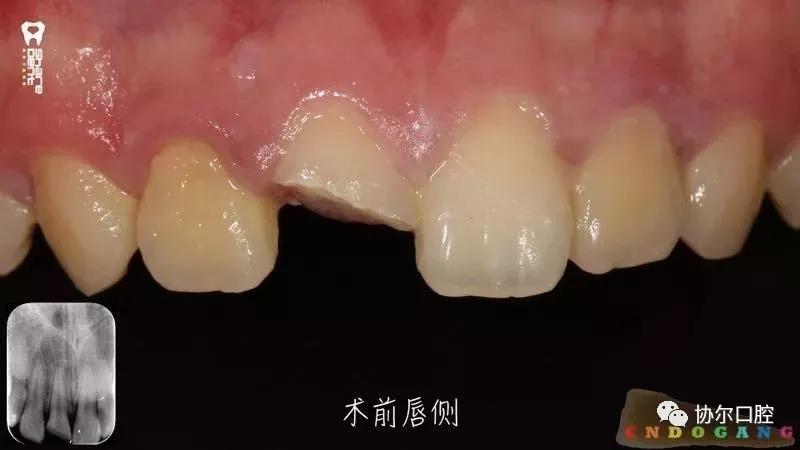

好多朋友都在问有没有前牙外伤折断后美塑树脂断牙显微再接的病例,正当小编“愁眉苦展”时,喻刚老师雪中送炭来了。15岁青少年断牙24小时,破镜重圆,修旧如旧。

病例刷一波